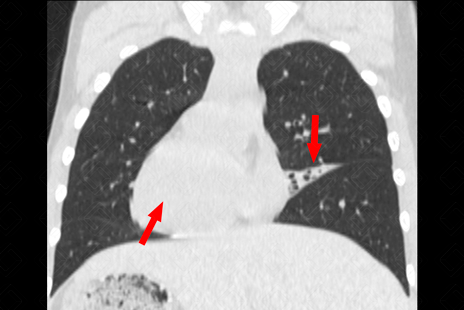

Texto alternativo para a imagem Figura 1. Créditos: Dra. Elazir Mota - Rio de Janeiro/RJ

Descrição da figura 1: Radiografia de tórax. Observe a presença de situs inversus totalis (seta vermelha no bordo cardíaco e fundo gástrico, ambos à direita). Há, ainda, opacidade borrando parcialmente o contorno cardíaco esquerdo (seta amarela).

• Radiografia de tórax: E m geral, observaremos espessamento das paredes brônquicas ou, em casos mais avançados, bronquiectasias. Sempre buscar por situs inversus (f igura 1) ;